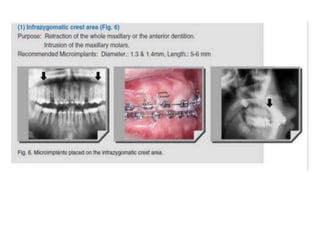

Sites of the implants